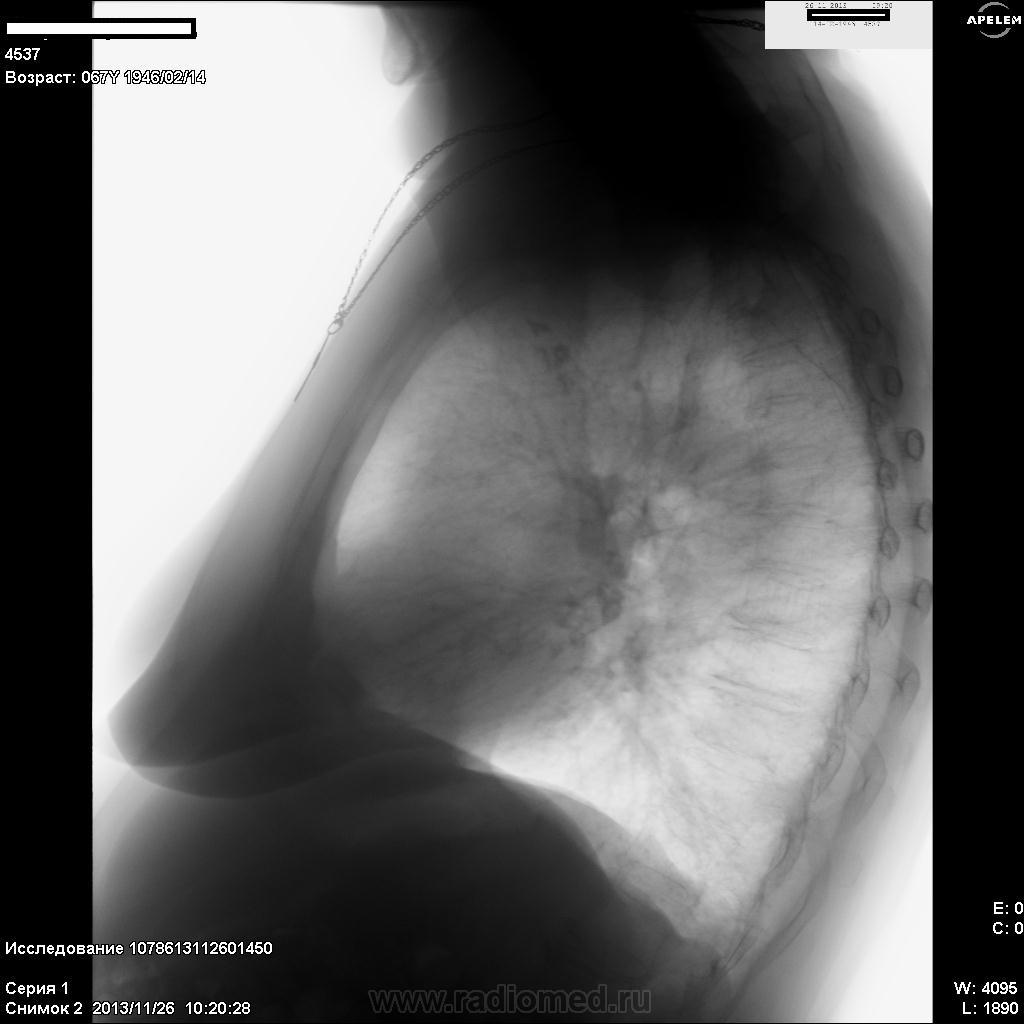

Пациентка, 67 лет. Жалоб нет. Профосмотр.

Плевральные наложения или перелом?

Сколиоз грудного отдела п-ка вправо. Остеопороз, остеохондроз, спорндилёз грудного отдела п-ка. Старый сросшийся перелом правой ключицы. Легочные поля эмфизематозны с признаками диффузного пневмосклероза.Обызвествление в паратахеальных лф/узлах справа.

Нет ли в данном случае расширение тени верхнего средостения, преимущественно вправо (укладка вроде симметричная)? С правым корнем все нормально?

Патологического расширения верхнего средостения не нахожу, думаю, что медиастинальную плевры справа оттесняет расширенная верхняя полая вена, ну, и/или ещё какой сосуд. А корень правый расширен и уплотнён сосудисто. Возраст. Бывает ещё и не то...